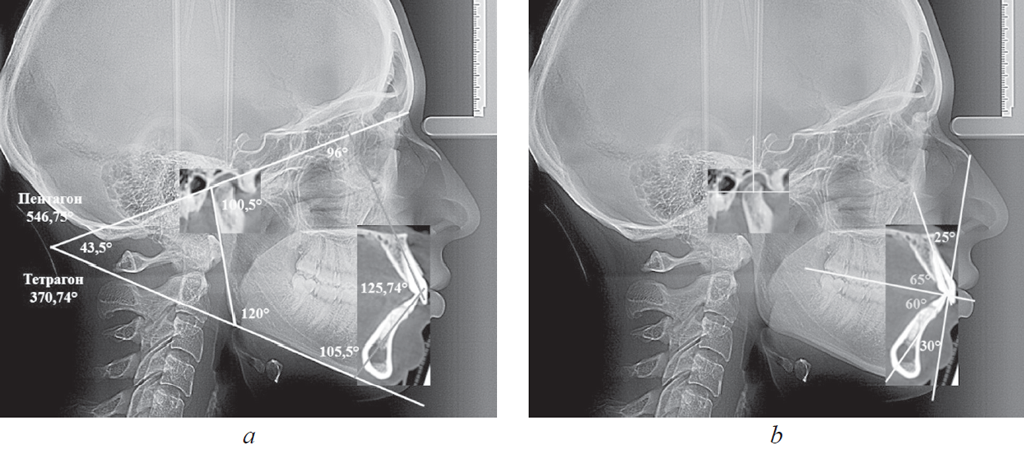

В вертикальном направлении соединяли точки N и Pg, полученную линию обозначали как «вертикальную линию лица». Касательная линия к ветви нижней челюсти (Ar – T1) с мандибулярной плоскостью образовывала угол нижней челюсти (рис. 1).

Рис. 1. Основные точки (a); линии используемые в качестве основных ориентиров для сопоставления рентгенограмм (b)

Fig. 1. Main points (a); lines used as the main reference points for the comparison of radiographs (b)

При совмещении зубочелюстного резцового фрагмента томограммы точку Pg томограммы совмещали с аналогичной точкой телерентгенограммы, расположенной на передней вертикали лица (N – Pg). При этом условные срединные вертикали медиальных резцов, соединяющие режущие края с верхушками корней зубов, совпадали с межрезцовыми линиями.

При совмещении фрагмента височно-нижнечелюстного сустава точку С томограммы совмещали с одноименным ориентиром телерентгенограммы. При этом ориентировались на соответствие расположения точек Ar (рис. 3).

Рис. 3. Измерение гнатических углов (а); оценка положения сустава и резцов на совмещенных рентгенограммах (b)

Fig. 3. Measurement of gnatic angles (a); assessment of the position of the joint and incisors on combined radiographs (b)

Полученные снимки позволяли проводить линейные и угловые измерения, а также переносить данные томограмм на телерентгенограммы. Как отмечено выше, рекомендуем измерять угол между линиями МL и KFL, а также углы, образованные линиями резцов с указанными линиями (верхнерезцовый и нижнерезцовый). В совокупности с межрезцовым углом нами предложено оценивать сумму указанных четырех углов (тетрагональный показатель), их величины могут быть использованы для определения типа роста лицевого отдела головы. К такому же показателю можно отнести сумму пяти углов: верхнерезцового, межрезцового, нижнерезцового, нижнечелюстного и суставного (пентагональный показатель).

Наложение резцового зубочелюстного сегмента на боковую телерентгенограмму давало возможность определить торковые (вестибулярно-язычные) значения углов наклона резцов к окклюзионной плоскости (ОL). При этом по обе стороны от линии ОL в вертикальном направлении строили перпендикулярные линии, которые являлись ориентиром для измерения углов инклинации (торка) по отношению к окклюзионной плоскости.